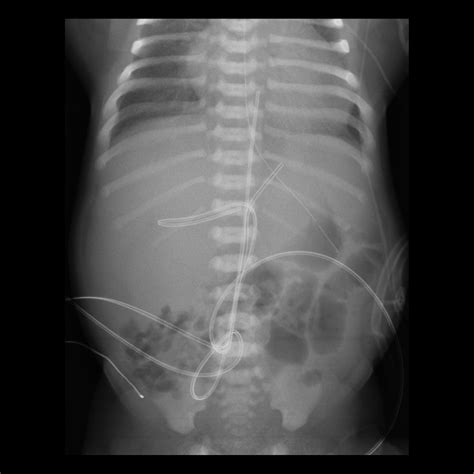

3. Insertion: The catheter is gently inserted into the umbilical vein, which is identified by its larger size and bluish color compared to the arteries. The catheter is advanced until it reaches the desired position, typically confirmed by ultrasound or X-ray.

5. Verification: The position of the catheter is verified using imaging techniques to ensure it is correctly placed in the inferior vena cava.

• Malposition: Incorrect placement of the catheter can lead to ineffective therapy or complications such as arrhythmias.